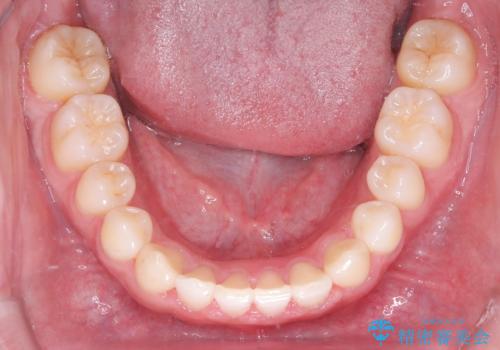

- 主訴:上の歯列の空隙を閉じたい

上顎前歯部に空隙が目立ちました。ワイヤー矯正、インビザライン(マウスピース矯正)どちらの方法でも適用症例と説明し、ワイヤー矯正治療(審美装置)を希望されました。

上顎歯列の空隙を閉じるのと一緒に、ディープバイト気味の被蓋も下顎前歯の圧下を行い改善しました。

矯正治療期間:2年ちょうど